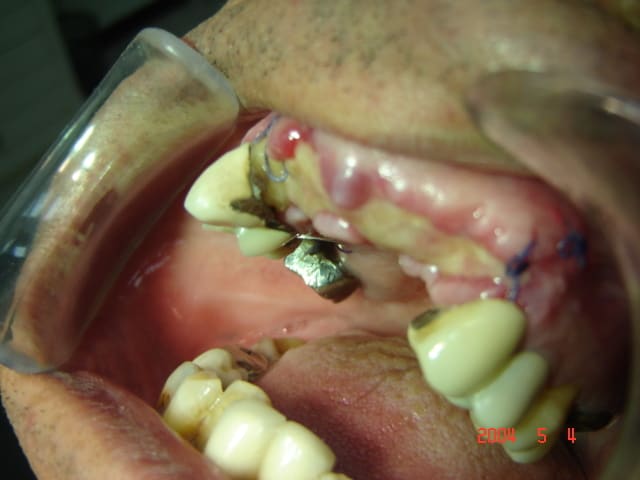

Comme promis , photos du cas a 22 jours post op.

qu'en pensez-vous

12/01/2006 à 13h56

et la troisieme .

> le lendemain je revois le patient et la j'ai

> constaté de petites expositions de la membrane

> entre les points de sutures .pas de douleurs , pas

> d'oedeme ,pas de signes inféctieux, bref silence

> clinique total. ce qui m'inquiete c'est les

> petites expositions de la membrane.

est-ce que j'ai une gueule d'une PETITE exposition? c'est une exposition universelle que tu nous fais là, ksou. mais, mais, ça ne veut pas dire que tout est perdu.